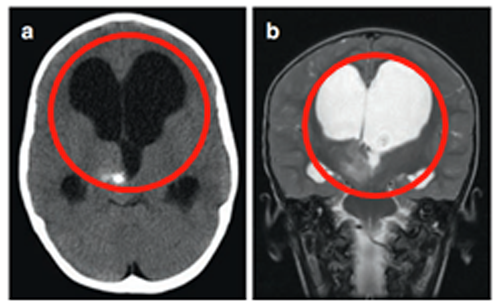

战胜脑干胶质瘤的他们。 这些影像,你是否觉得熟悉? 对于脑干胶质瘤患者而言,这些影像再眼熟不过病情的宣告,往往始于这一张张片子。 人生就像打扑克,总会抓到几张烂牌。而这一张张...